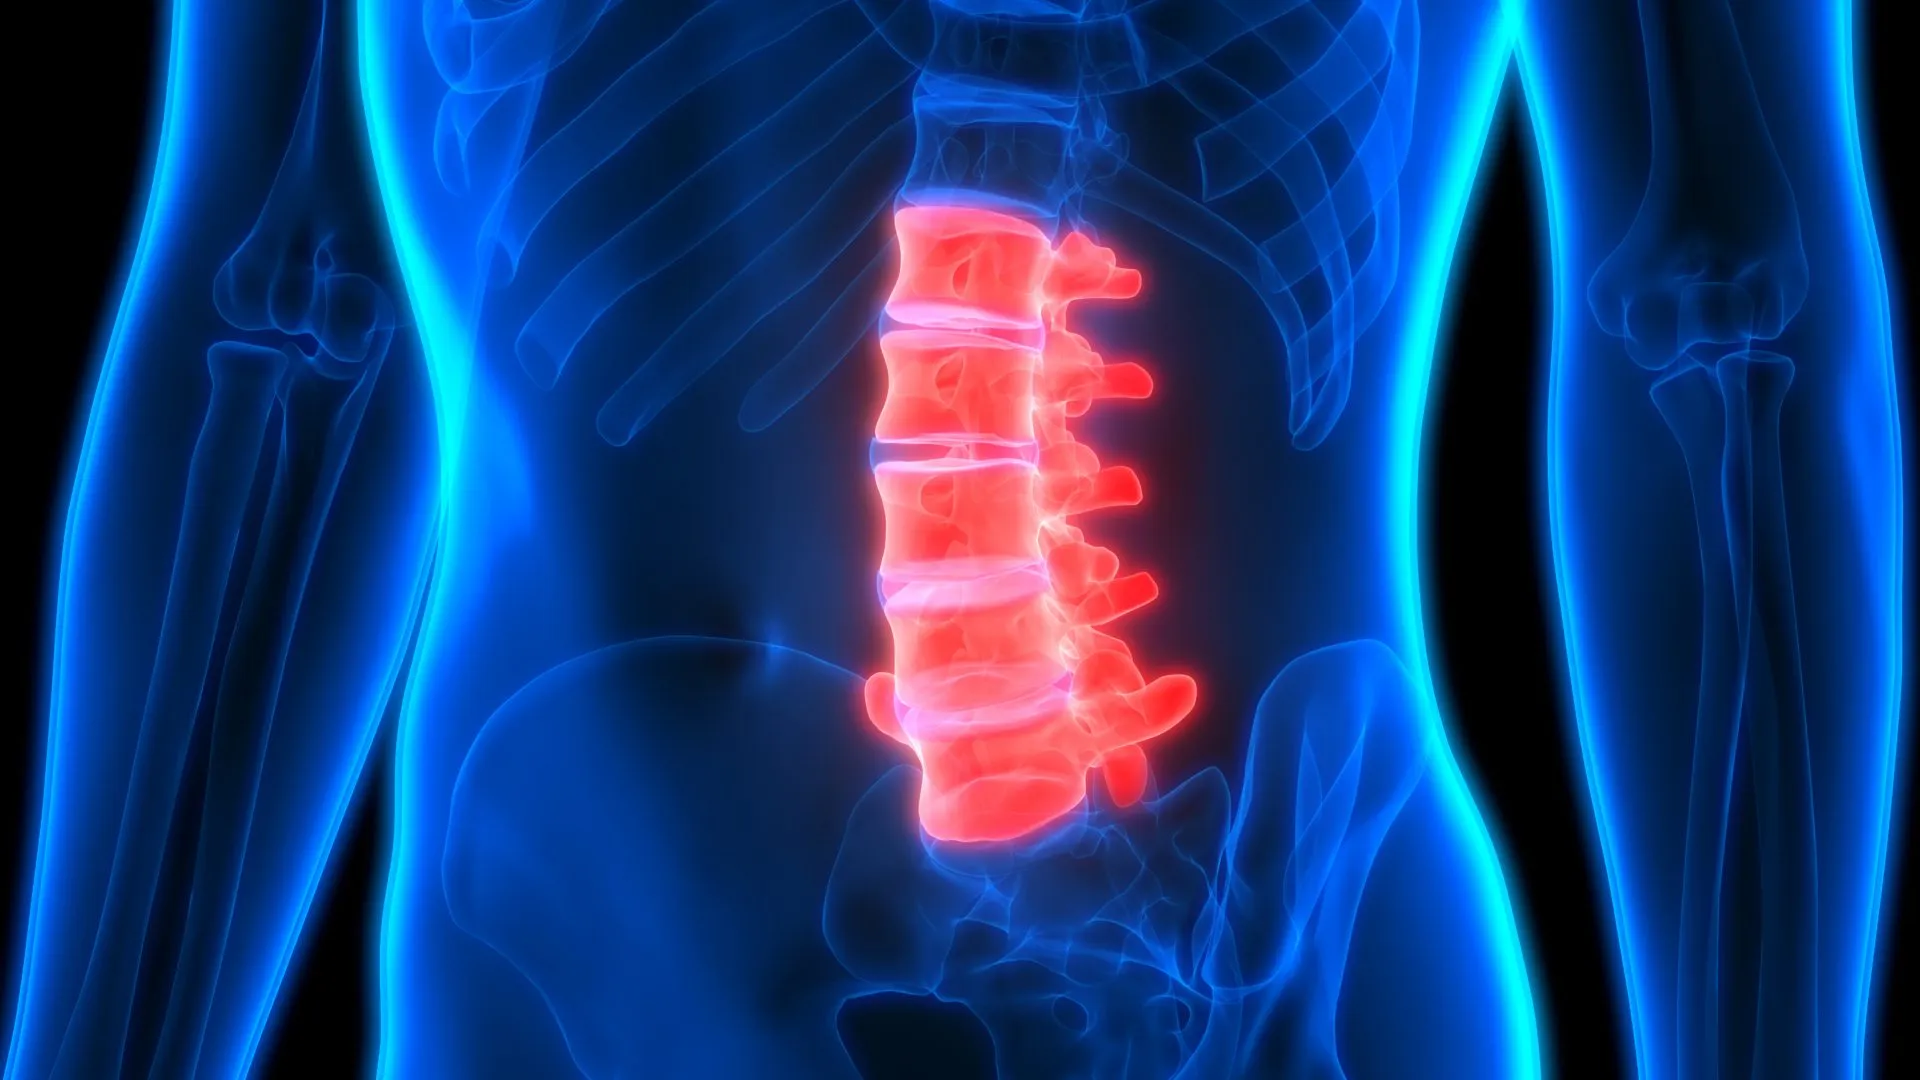

ستون فقرات، بهعنوان محور اصلی حرکت و پشتیبانی بدن، تحت تاثیر عوامل مختلفی، ممکن است دچار فرسایش و التهاب شود. آرتروز ستون فقرات، که به آن اسپوندیلوز نیز گفته میشود، یک بیماری دژنراتیو است که با تحلیل رفتن غضروف مفاصل و دیسکهای بین مهرهای همراه است. این فرایند میتواند...

سندروم دم اسبی یا سندرم کودا اکوینا، یک اختلال عصبی نادر است که به دلیل فشار شدید یا فشردگی ریشههای عصبی در انتهای نخاع، که به آن دم اسبی (cauda equina) گفته میشود، به وجود میآید. این بیماری میتواند عوارض جدی و دائمی، از جمله فلج، بیاختیاری ادرار و...

فتق یا بیرون زدگی دیسک یکی از مشکلات شایع ستون فقرات است که به دلیل فشار یا پارگی در دیسکهای بین مهرهای ایجاد میشود و باعث درد، بیحسی و ضعف در اندامها میشود. معمولا افرادی که بیشتر از ۳۰ سال دارند دچار این بیماری میشوند، اما سن تنها عامل...

آرتروز کمر، یا استئوآرتریت ستون فقرات، یک بیماری مفصلی است که با تخریب تدریجی غضروف مفصلی بین مهرهها مشخص میشود. این غضروف به عنوان یک بالشتک عمل میکند و به مفاصل اجازه میدهد تا به آرامی روی هم بلغزند. زمانی که این غضروف تخریب شود، استخوانها به هم ساییده...